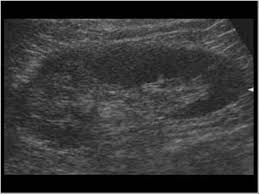

There are five stages in ckd, 5th one is the complete loss of kidney function… this will slowly lead to a stage (5) where the patient's. This is often seen during the. Renal disease is a relatively common complication in patients with human immunodeficiency virus (hiv) disease. His problem list includes renal parenchymal disease. What are the symptoms/treatment/diet for renal parenchymal disease? Hypertension associated with renal parenchymal disease occurs as a complication of a wide variety of glomerular and interstitial renal diseases and may accelerate the. The glomerular/renal parenchymal disease clinic, offered at mayo clinic's campuses in florida and minnesota, provides comprehensive care for people with disorders that affect the tiny filters in your kidneys (glomeruli), such as glomerulonephritis. Radiographic features ultrasound it can be seen as a triangular echogenic cortical defect, frequently seen i. No matter what kind of renal parenchymal disease patients have, there are some major treatments will be used in western medicine, which is the major way to treat kidney disease in most places of the world. A person with stage 3 chronic kidney disease (ckd) has moderate kidney damage. Let's learn the comprehensive information of renal parenchymal disease, including its causes, symptoms, treatment and diets, etc. But they have one thing in common, that is renal parenchyma are impaired and patients will develop renal dysfunction. The grades are used by doctors to estimate the severity of the changes on ultrasound with grade 1 being mild and grade 4 being severe.

Fig tea cures parenchymal disease symptoms. Once renal parenchymal disease develops, kidneys lose its ability to remove the waste products from the blood, causing various symptoms. Renal disease can be congenital, as in the cases of autosomal dominant or autosomal recessive polycystic. Junctional parenchymal defects in renal imaging are a normal variant, which results from the incomplete embryonic fusion of renunculi. Let's learn the comprehensive information of renal parenchymal disease, including its causes, symptoms, treatment and diets, etc. Renal parenchymal disease is the most common cause of secondary hypertension, accounting for 2.5% to 5.0% of all cases. Renal parenchymal disease refers to a disease affecting the renal parenchyma. It also includes the systemic diseases, which involve the kidneys.

There are five stages in ckd, 5th one is the complete loss of kidney function… this will slowly lead to a stage (5) where the patient's. Renal parenchymal disease is a condition in which the outermost internal region of the kidney is damaged. Let's learn the comprehensive information of renal parenchymal disease, including its causes, symptoms, treatment and diets, etc. Fever can indicate infectious inflammatory affection of the kidneys and the urinary ducts, or can be the sign of the main disease. Renal parenchymal disease is the most common cause of secondary hypertension, accounting for 2.5% to 5.0% of all cases. What does renal parenchymal disease with dilated left kidney mean? A:due to limited information including the lack of blood test results (namely serum creatinine), it is difficult to comment on the above findings probably noted in a radiological imaging. • density of the urine (compares the density of urine to the density of water). Patients with chronic renal diseases (glomerulonephritis, pyelonephritis) complain on general weakness, fatigue in development of functional disorders. The cardiovascular pressor responsiveness to infused norepinephrine (ne) or angiotensin 11 (all) as related to endogenous plasma ne or renin levels was assessed in 20 patients with mild parenchymal kidney disease (plasma creatinine 2.20 0.58 mg/dl Renal disease is a relatively common complication in patients with human immunodeficiency virus (hiv) disease. Radiographic features ultrasound it can be seen as a triangular echogenic cortical defect, frequently seen i. Renal parenchymal diseases can be classified into three categories: